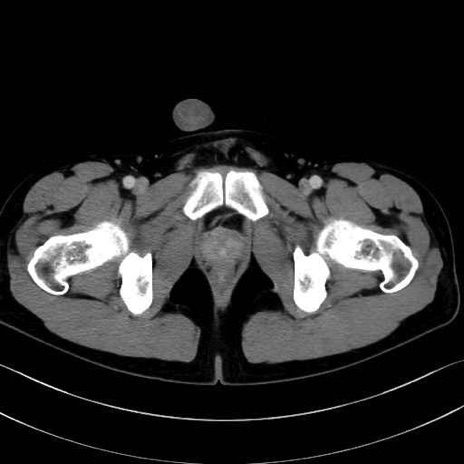

縫工筋 (Sartorius)

大腿直筋 (Rectus femoris)

外側広筋 (Vastus lateralis)

中間広筋 (Vastus intermedius)

恥骨筋 (Pectineus)

長内転筋 (Adductor longus)

短内転筋 (Adductor brevis)